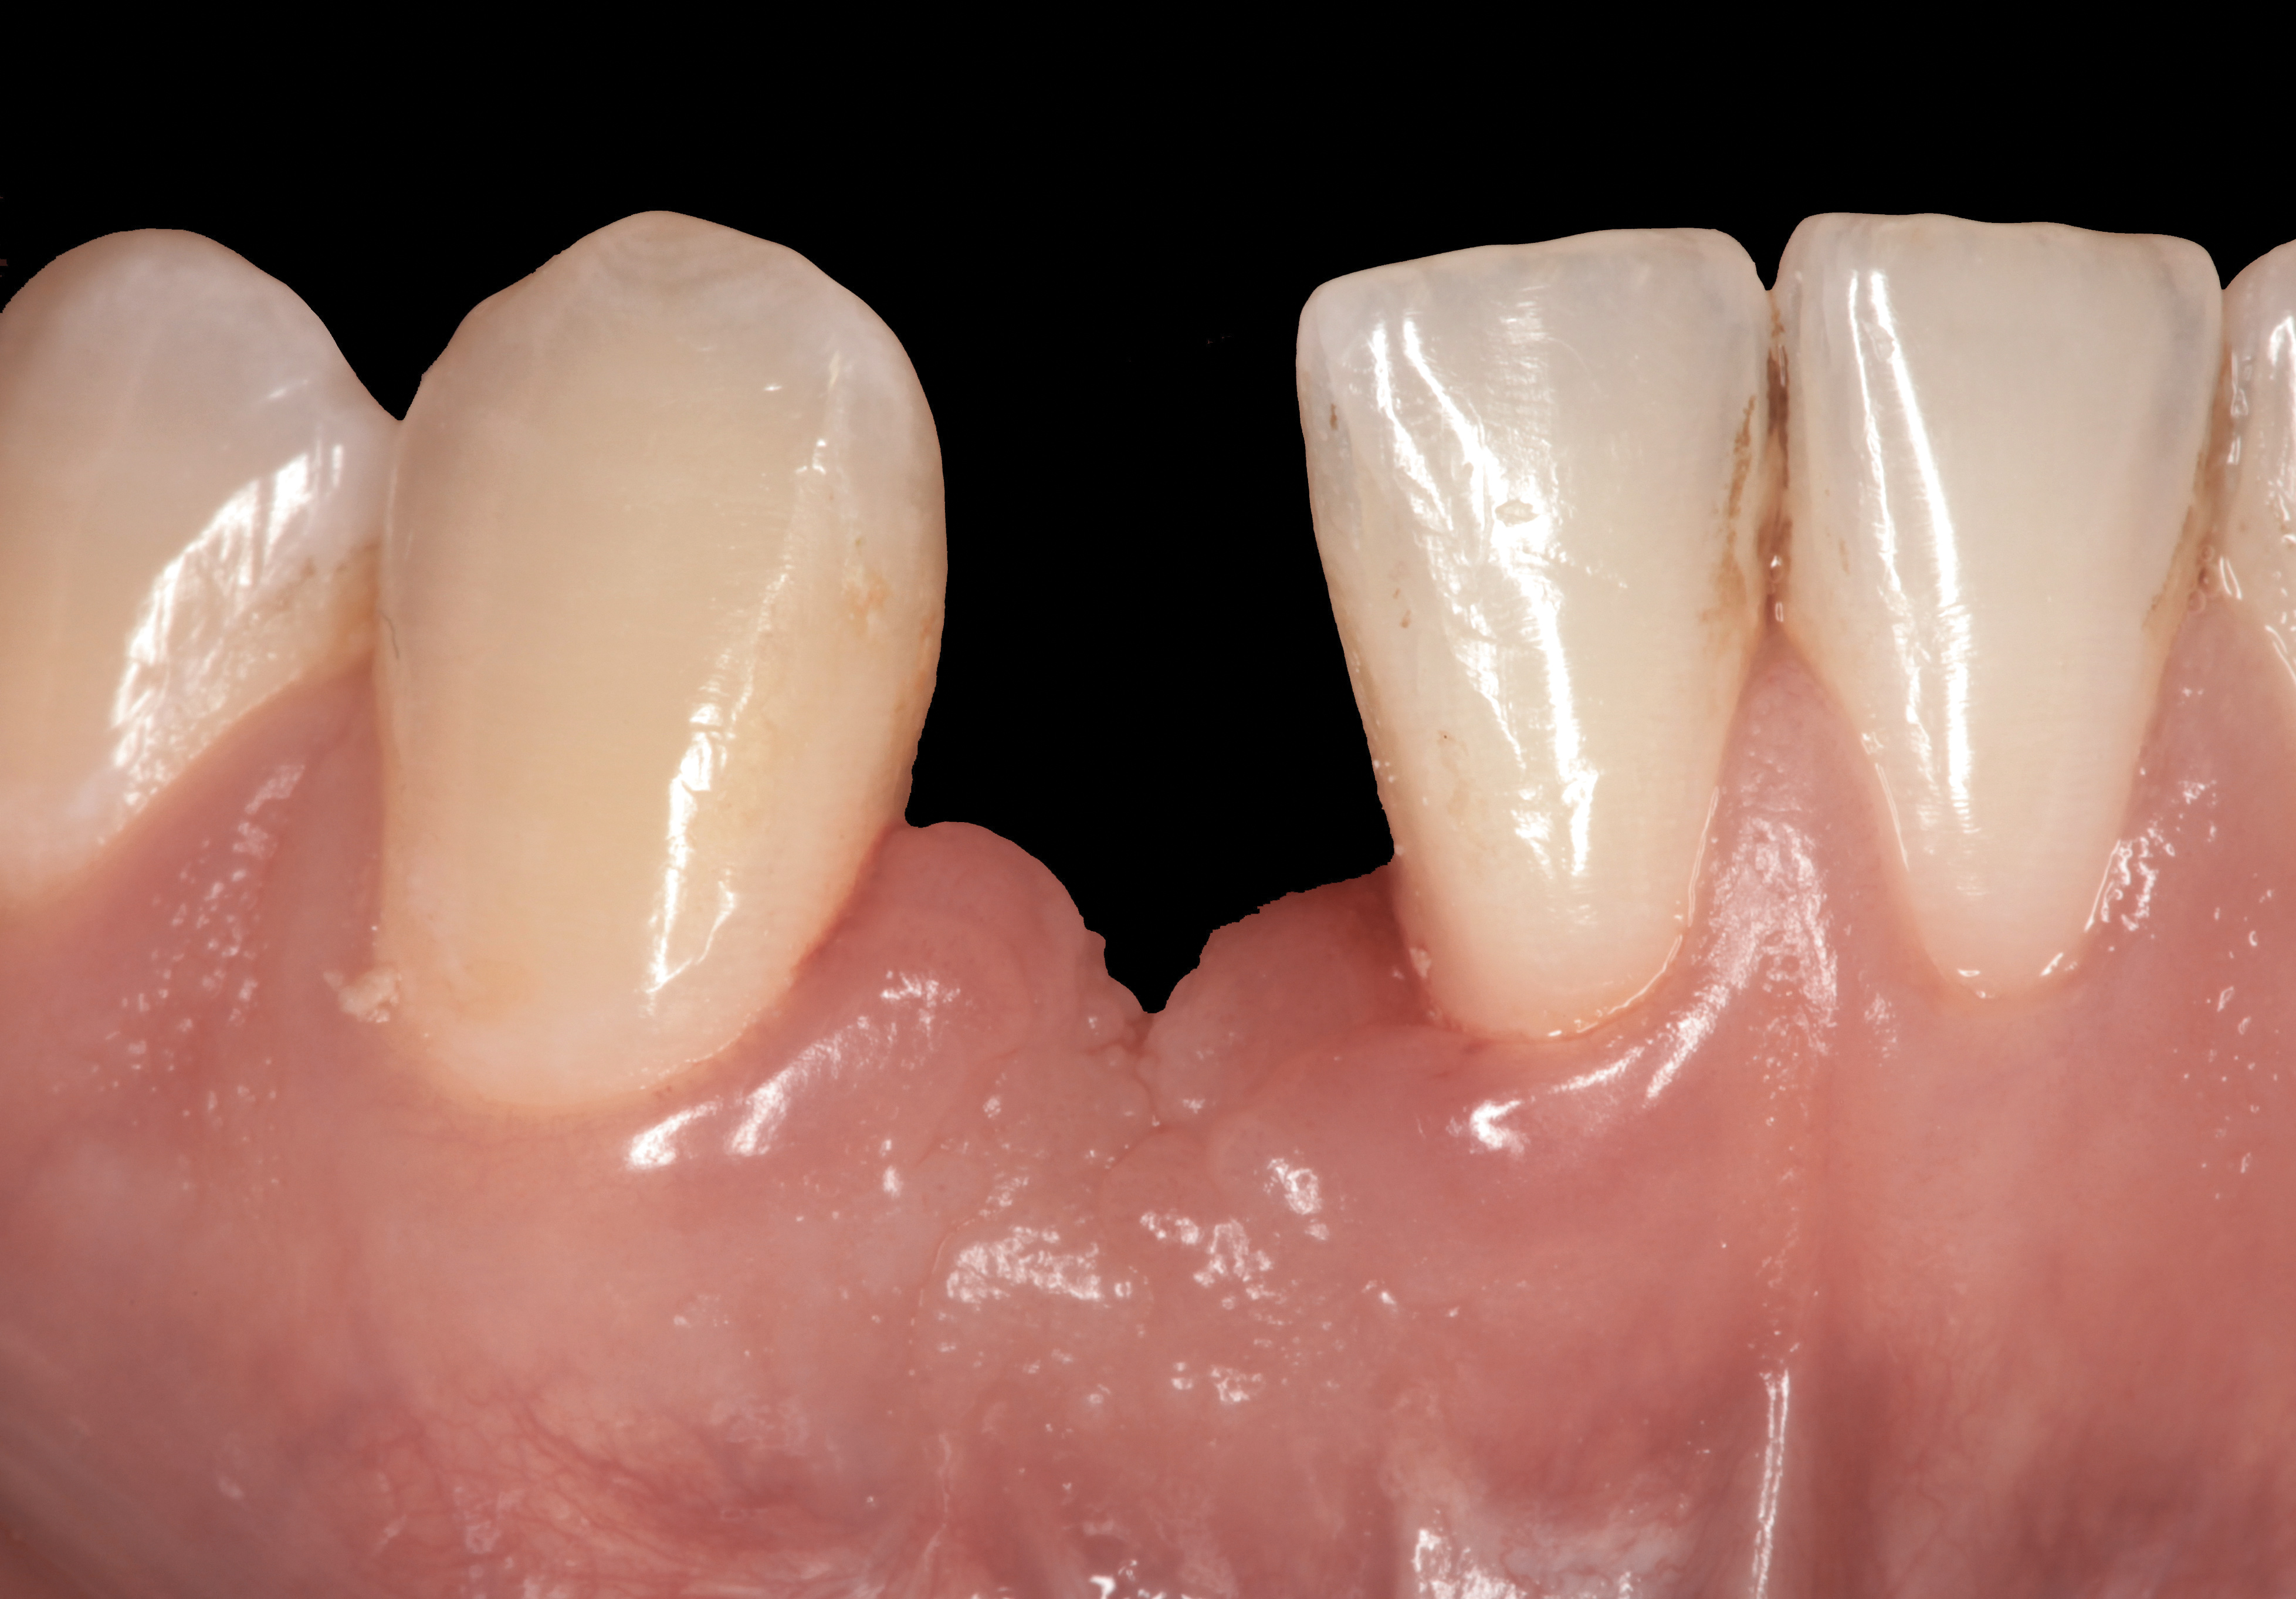

The following case report provides an example of this case scenario: A 24-year-old white male presented with congenitally missing tooth No. 26 restored with a single-tooth cement-retained implant restoration. The implant was placed excessively to the facial aspect of the edentulous site and too shallow, and the periodontal phenotype was thin scalloped (Figure 32). In an effort to mimic the lost midfacial soft tissues, pink ceramics were used as a cosmetic facade. Even though the restoration was not in the esthetic zone, the patient was highly displeased with the esthetic outcome and sought remediation.

The crown and screw-retained custom abutment were removed, and a surgical cover screw was placed into the implant, thereby allowing spontaneous gingival augmentation in situ (Figure 33 and Figure 34). Note that the lingual aspect of the implant site was significantly more coronal than the labial aspect, which was positive because the defect would be limited to a facial–lingual defect. A fixed RBR bridge was cemented on the adjacent teeth and used as a tooth-supported transitional provisional restoration (Figure 35). A few weeks were allotted to let the soft tissue heal and migrate around the cover screw (Figure 36) to see if there would be complete coverage, thereby allowing a soft-tissue augmentation procedure to be performed with primary flap closure as in clinical scenario No. 2. The major obstacle in achieving a positive tissue response was that the implant depth was also deficient because the implant–abutment connection was at the level of the free gingival margin. It was decided that the best treatment option would be to remove the implant. A high-powered reverse-torque device (Fixture Remover Kit, NeoBiotech, www.neobiotechus.com) was used to remove the implant atraumatically (Figure 38 through Figure 41). The implant socket was allowed to heal for several months not unlike an extracted tooth (Figure 42). A new implant was placed in a better position from both a restorative and esthetic perspective (Figure 43), and after a few months of healing, a new crown was made (Figure 44). A satisfactory functional and esthetic result was achieved (Figure 45 and Figure 46) without employing pink porcelain.

Fig 32. A dissatisfied patient presented with significant midfacial recession of implant restoration of tooth No. 26. Pink ceramic material was used unsuccessfully to prosthodontically compensate for the lost midfacial tissue.

Fig 33. Excessive facial angulation of the implant placement shown with an abutment driver in the access screw hole.

Fig 34. A surgical cover screw was placed in an attempt to decoronate the implant and gain soft-tissue coverage in situ.

Fig 35. A transitional resin-bonded-retained (RBR) bridge that was tooth supported was placed to allow soft-tissue maturation.

Fig 36. Two weeks after RBR placement, the soft tissue did not adequately cover the implant. The problem was in poor implant angulation and proper depth to allow the soft tissues to cover over.